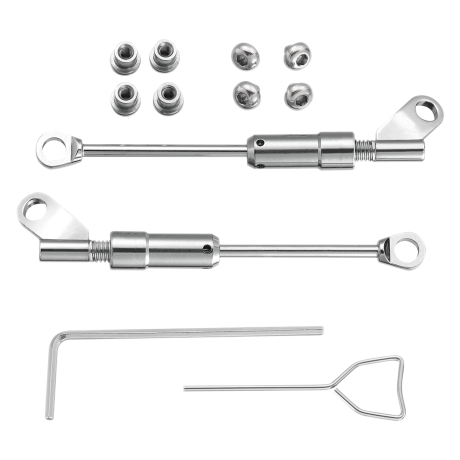

Арт:

307-1010

В наличии

Арт:

307-1012